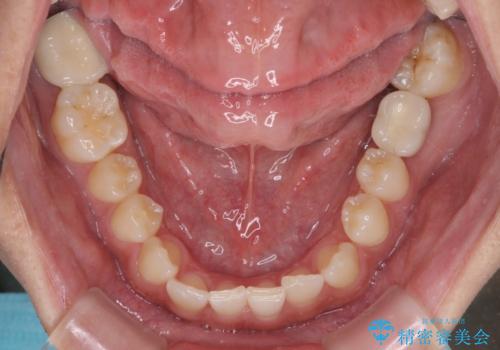

下顎前歯に叢生がありましたが、特に気にしていらっしゃいませんでした。

下顎前歯の叢生解消も提案しましたが、上顎の隙間が閉じたことで満足されました。